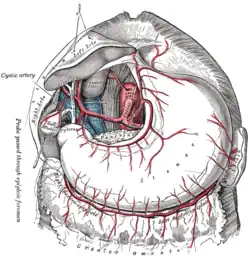

The celiac artery and its branches. Transverse section of the human spleen, showing the distribution of the splenic artery and its branches.